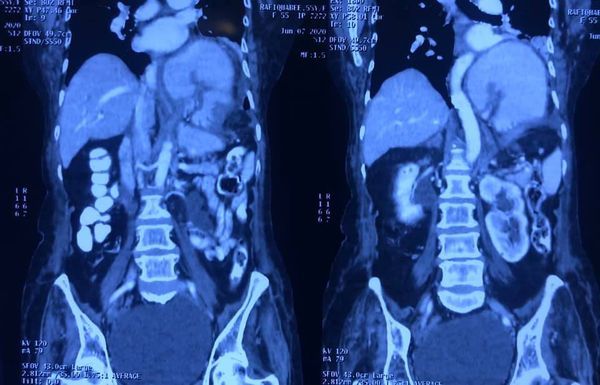

Interesting Images March 2019 : Patient came with an early stage carcinoma rectum, underwent Hemicolectomy surgery then lost to follow-up. Later after 9 month patients presented to us with Stage 4 disease (Carcinoma colon with Liver secondaries). Then we started her on treatment with Chemotherapy along with Monoclonal antibodies with six cycle of above said treatment patient achieved near complete remission. We could achieve very good results with chemotherapy even in patients with Stage 4 disease (Carcinoma colon with Liver secondaries).